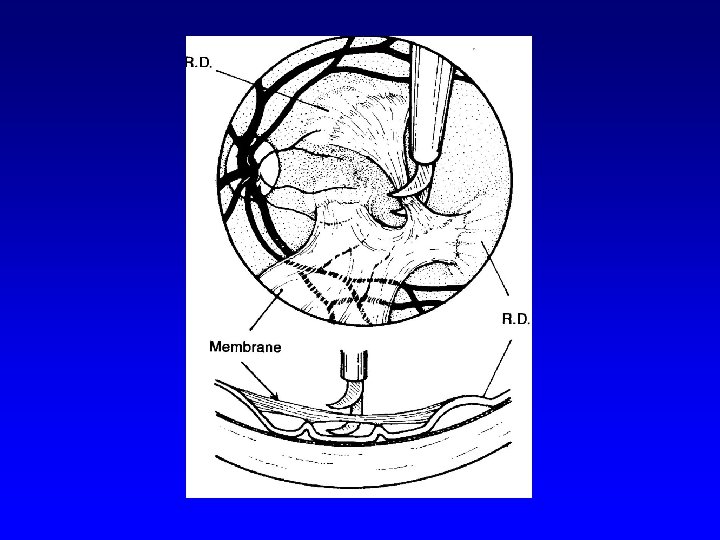

Proliferative DR (PDR) • • • Light Intermediate Fully advanced VH- vitreous hemorrhage, PRHpreretinal hemorhage, TRD- retinal detachment at center of macula

Fully advanced PDR

Fully advanced PDR

Surgical therapy of DR • Pars plana vitrectomy- (Machemer, Parel – 1970)